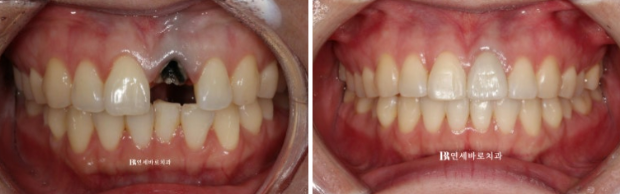

잇몸섷영을 해서 과하게 자라 내려온 잇몸을 제거했습니다.

원래 잇몸라인을 회복한 후에

치아를 깨끗하게 정리하고 옆치아 색에 맞추어 크라운 보철에 들어갑니다.

23.07

최종 크라운까지 예쁘게 들어갔습니다.